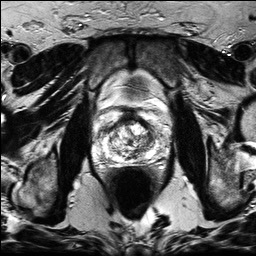

Denoising diffusion probabilistic models (DDPMs) have achieved unprecedented success in computer vision. However, they remain underutilized in medical imaging, a field crucial for disease diagnosis and treatment planning. This is primarily due to the high computational cost associated with (1) the use of large number of time steps (e.g., 1,000) in diffusion processes and (2) the increased dimensionality of medical images, which are often 3D or 4D. Training a diffusion model on medical images typically takes days to weeks, while sampling each image volume takes minutes to hours. To address this challenge, we introduce Fast-DDPM, a simple yet effective approach capable of improving training speed, sampling speed, and generation quality simultaneously. Unlike DDPM, which trains the image denoiser across 1,000 time steps, Fast-DDPM trains and samples using only 10 time steps. The key to our method lies in aligning the training and sampling procedures. We introduced two efficient noise schedulers with 10 time steps: one with uniform time step sampling and another with non-uniform sampling. We evaluated Fast-DDPM across three medical image-to-image generation tasks: multi-image super-resolution, image denoising, and image-to-image translation. Fast-DDPM outperformed DDPM and current state-of-the-art methods based on convolutional networks and generative adversarial networks in all tasks. Additionally, Fast-DDPM reduced training time by a factor of 5 and sampling time by a factor of 100 compared to DDPM. Our code is publicly available at: https://github.com/mirthAI/Fast-DDPM.